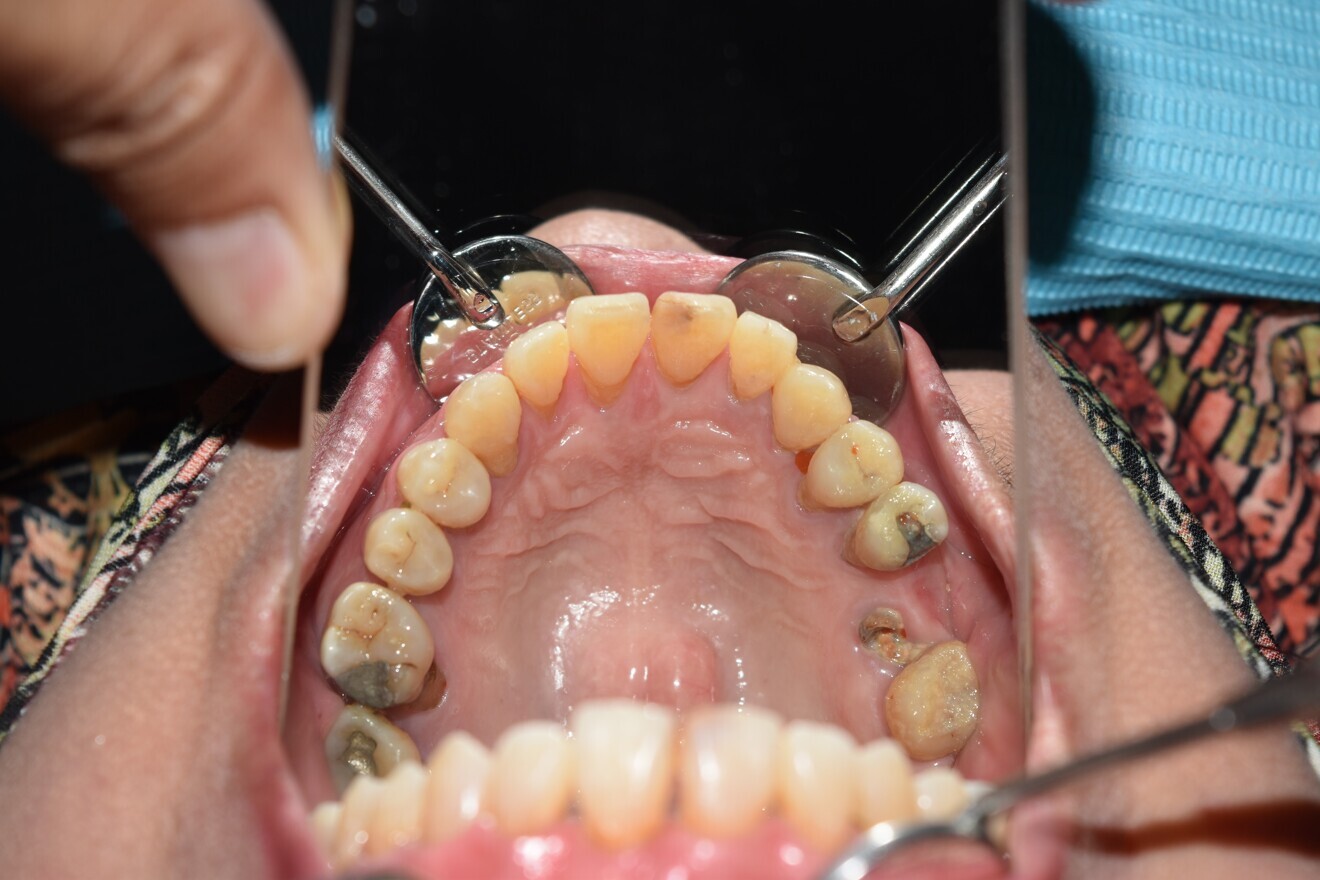

Intra-oral findings:

Class I malocclusion with poli diastemas in both upper and lower arch.

Overbite= 1mm Overjet = 3mm

No molar classification (absence of molars)

Class I canine on right and left side.

Upper midline (mesial to 11) on with face.

Lower midline on with the chin.

Missing 18, 16, 25,26, 28, 36, 47 and 48.

20-30% vertical bone loss upper anterior region.